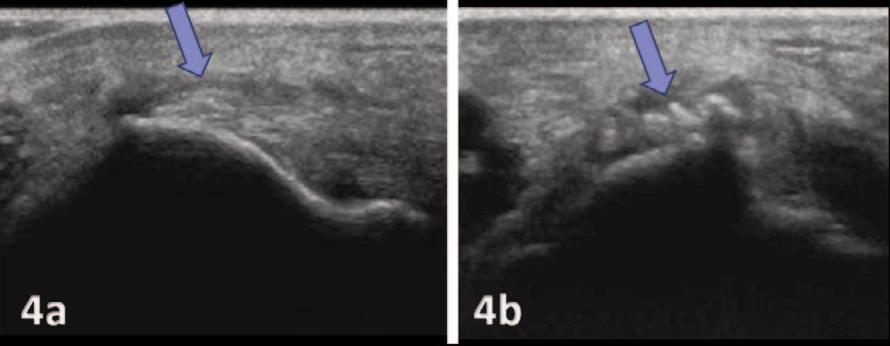

135 Diagnostic Musculoskeletal Ultrasound for the Evaluation of the Lateral Elbow: Implications for Rehabilitation Providers.

Manske RC, Wolfe C, Page P, Voight M.